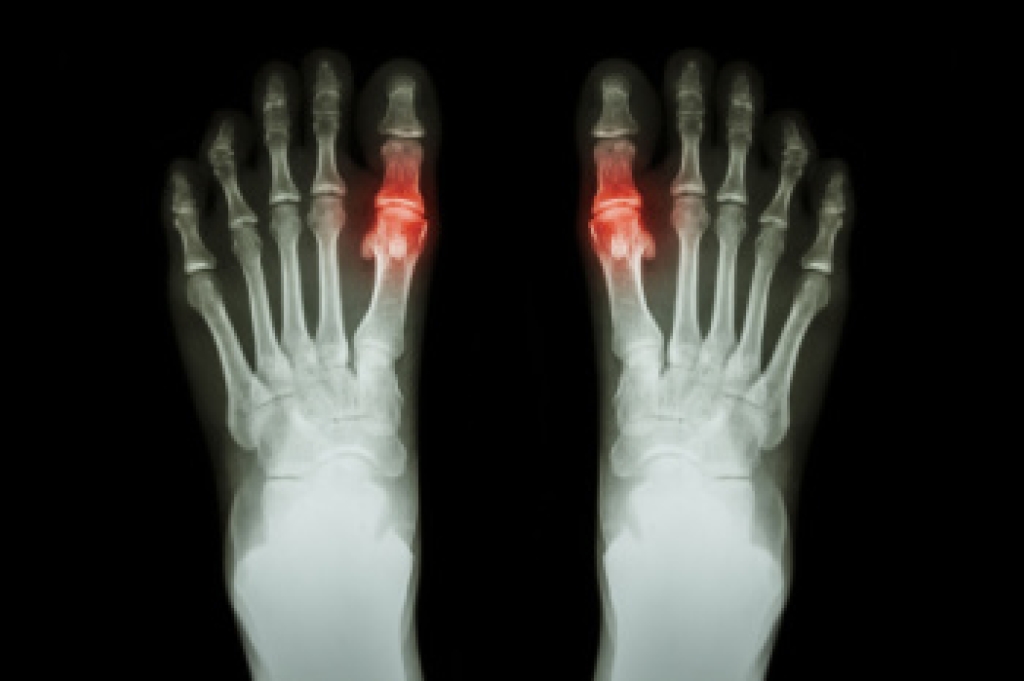

Gout is a form of arthritis caused by the buildup of uric acid crystals in the joints. It often affects the big toe, but can also impact other joints such as the knees, ankles, and wrists. A gout attack typically comes on suddenly, causing intense pain, swelling, and redness in the affected joint. These flare-ups may occur after consuming foods high in purines, such as red meat, seafood, and alcohol, which increase uric acid levels in the blood. Other risk factors include obesity, dehydration, and certain medications. To diagnose gout, a doctor may examine the affected joint, perform blood tests to check uric acid levels or take a sample of fluid from the joint to look for uric acid crystals under a microscope. If you are suffering from gout, it is suggested that you contact a podiatrist who can offer you effective relief and prevention methods.

Gout is a form of arthritis that is characterized by sudden, severe attacks of pain, redness, and tenderness in the joints. The condition usually affects the joint at the base of the big toe. A gout attack can occur at any random time, such as the middle of the night while you are asleep.

- Inflammation and Redness -Affected joints may become swollen, tender, warm and red